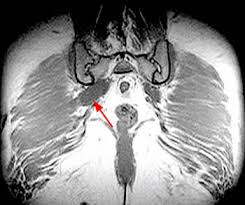

The Radiology Assistant Perianal Fistulas

The Radiology Assistant Perianal Fistulas from radiologyassistant.nl